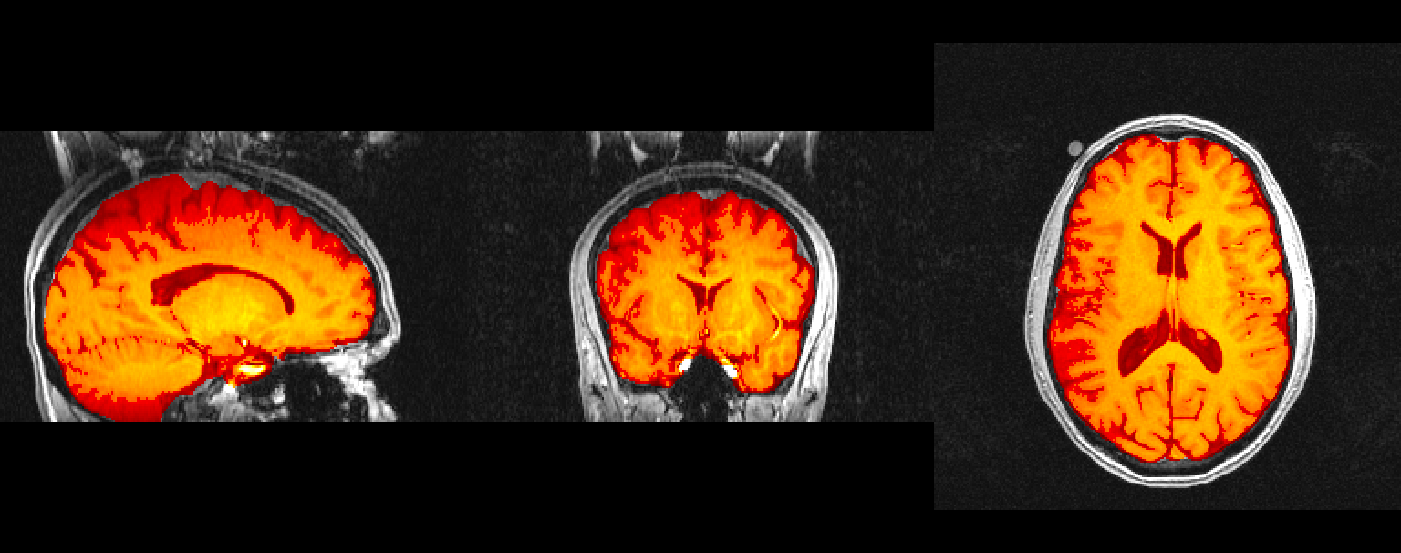

fsleyes structural -cm blue structural_fov structural_fov_brain -cm hot &

You are looking at three images here - the blue one in the background (if you can see it) is the raw T1 image, the grey one is the T1 image after the FOV has been tightened with robustfov, and the red-yellow image is the T1 image after non-brain voxels have been zeroed out by bet.